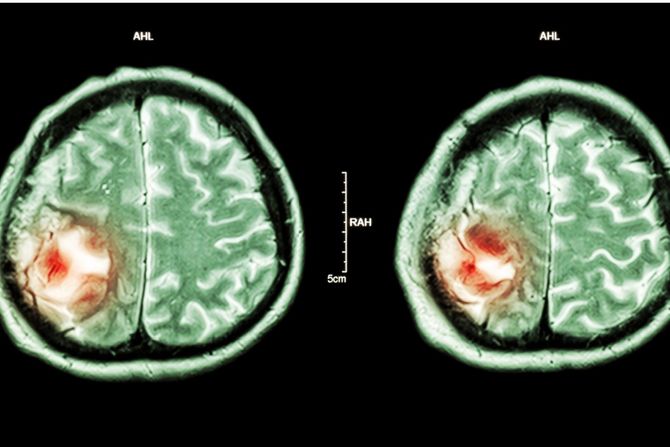

Tumor mozga određuje se kao abnormalni rast ćelija unutar lobanje. Tumor je nekada benigni, to jest dobroćudan, ili zloćudan - maligni. Lekari kažu da su bez obzira na prirodu, tumori mozga uvek ozbiljne bolesti jer pritiskaju bitne centre mozga i izazivaju neurološke i psihičke probleme. U nekim situacijama se nepovratno menja ličnost čoveka. Veseo i druželjubiv čovek, dobrica i pitom, može zbog bolesti da se povuče u sebe, počne da izbegava druge osobe ili čak postane agresivan.

Mesto tumora mozga može da utiče na raspoloženje i ponašanje zato što različiti delovi mozga kontrolišu različite aspekte ličnosti, raspoloženja i ponašanja. Tumori mogu na više načina da poremete ove funkcije.

Frontalni režnjevi u mozgu kontrolišu motivaciju, samokontrolu i impulsivnost. U slučaju da tumor ošteti oba frontalna režnja, moguće je da se osoba povlači i da ne uživa u aktivnostima koje su joj ranije bile zadovoljstvo. Kod nekih osoba može da se javi i gubitak kontrole impulsa.

Insula je kompleksan deo moždane kore koji reguliše emocije. Tumori u insuli mogu da izazovu razne emocionalne simptome /anksioznost, osećaj ubrzanog rada srca, paniku.